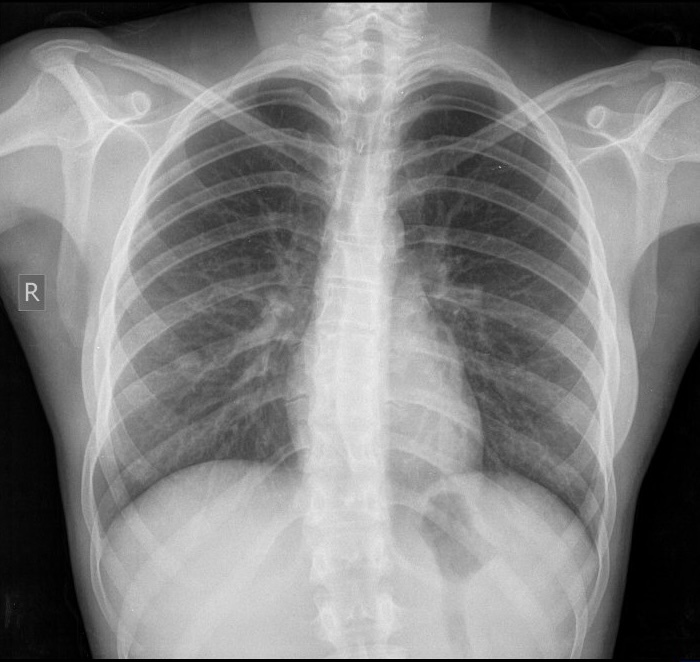

Tos: ¿Cómo se realiza la evaluación?

El estudio de la tos comprende, por un lado, el examen del reflejo tusígeno y su sensibilidad y, por otro, su caracterización cuantitativa y cualitativa como expresión sintomática de una…